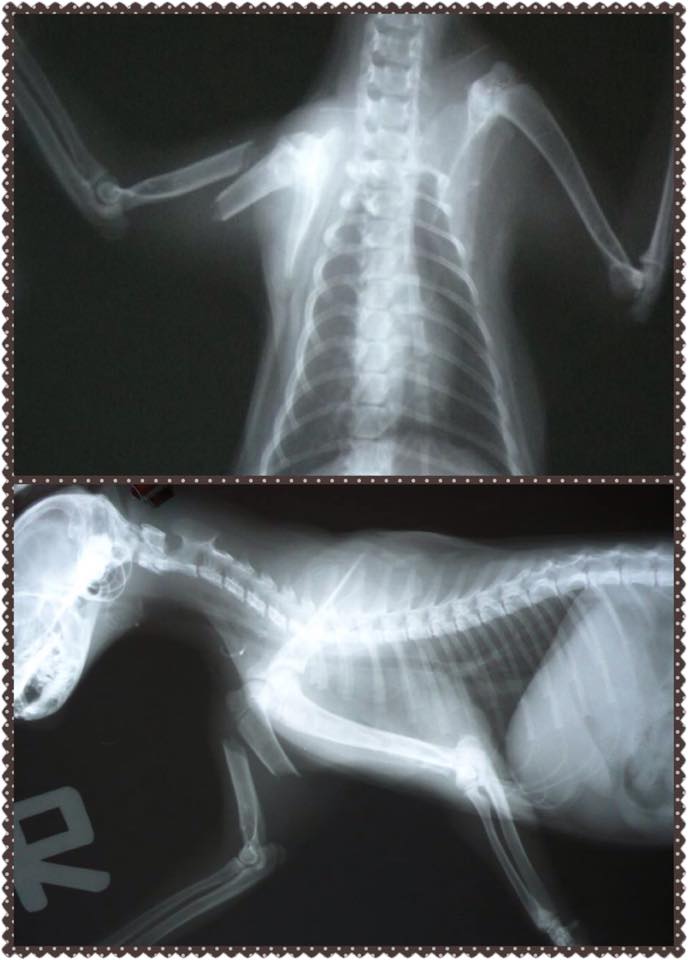

11/3晚上志工在誘捕貓咪時發現有隻大概5個月的小黑貓腳怪怪的,好像斷掉了,而且他處在的環境實在是很糟糕,需要跳上跳下,非常危險的高樓層,而且鄰居對流浪貓很不友善,怕是被人驅趕歐打所造成的傷害。

後來連同要結紮的貓咪還有受傷的貓咪一起送長沁動物醫院,拍了X光後,確診為右前腳上肢斷裂。